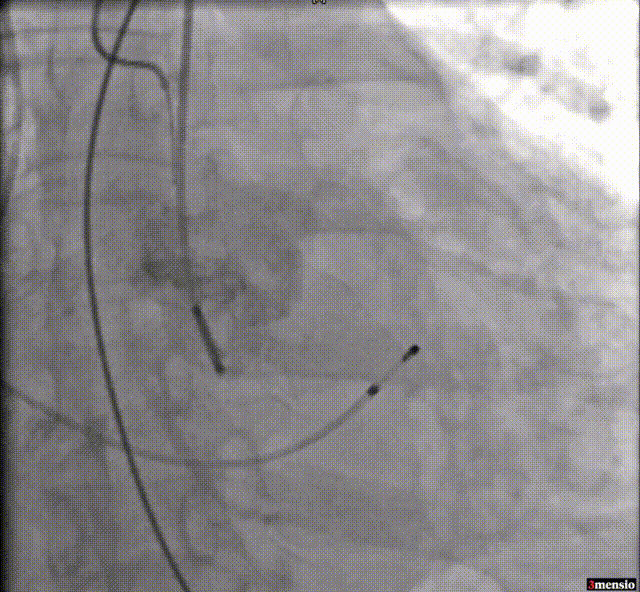

2.经皮左侧腋动脉穿刺,建立腋动脉入路;

腋动脉穿刺建立入路